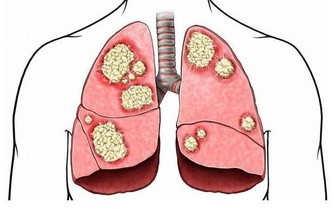

近十幾年來,生薑在紓緩疼痛、輔助治療關節炎上的效果倍受矚目。

風濕病專家在250名骨關節炎患者中進行過一項實驗:

在6週的療程中,一組患者每天兩次服用含有生薑成分的藥物255毫克,另一組患者則服用不含生薑成分的藥物。

2/3服用了含有生薑成分藥物的患者反映,他們感覺病痛減輕,其效果遠遠高於另一組的患者。

貼在疼痛處,可祛風除濕,消腫止痛,輔助治療各種關節炎。

對防治關節炎,寒濕侵襲所致的風濕病、頸椎疼痛等,都有較好治療效果。